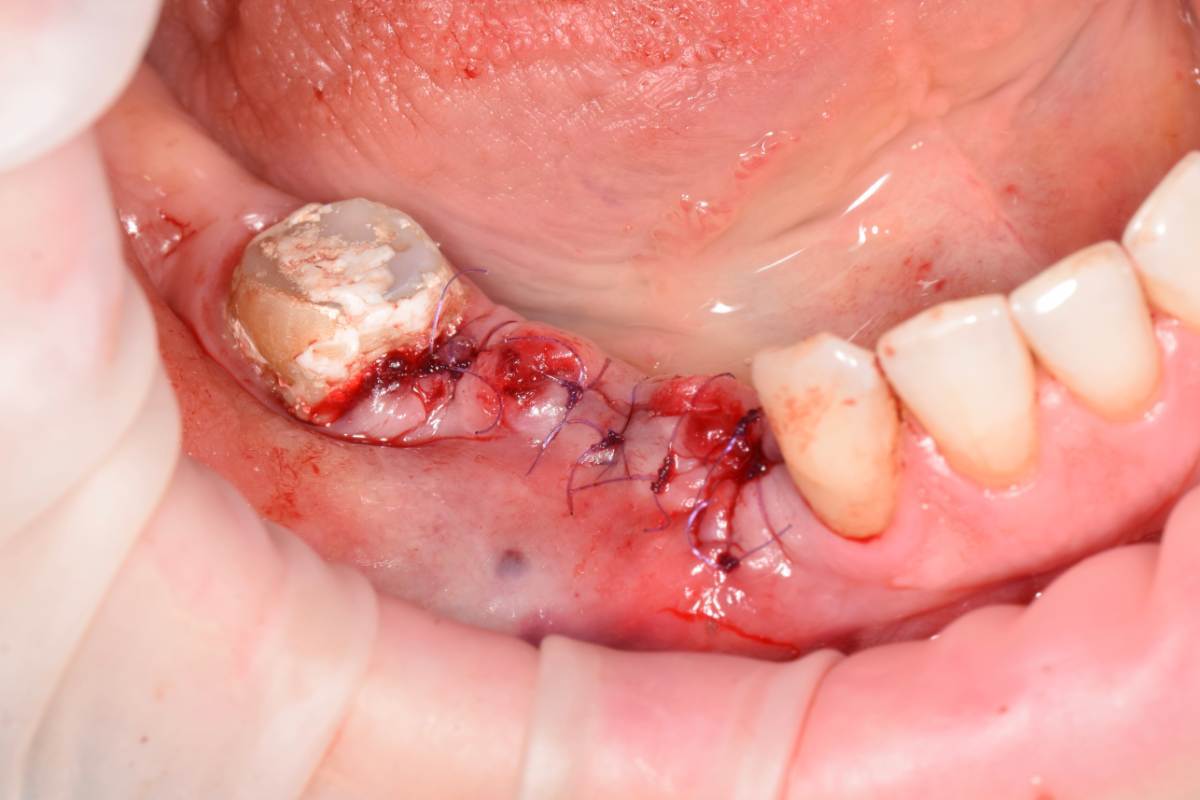

Fin Опубликовано 5 июня, 2025 Поделиться Опубликовано 5 июня, 2025 Здравствуйте коллеги. Хотел бы представить вашему вниманию первую часть кейса по восстановлению 4 сегмента. Перелом зуба 4.5 под мостовидным протезом 4.7-4.4. 4.7 решено оставить до последующего повторного протезирования При планировании имплантации вестибулярное оголение имплантата на 1.5-2мм в области 3. 4. Дефицит керотинизированной слизистой оболочки. Более глубокое положение имплантата приведет к чрезмерному количеству сзизистой оболочки в 7-8 мм. Решено не пытаться использовать ССТ с целью перекрытия оголенного имплантата а попробовать технику морковки профессора Кюри. 1 этап операции. Удаление зуба 4.5, подготовка костного ложа под имплантаты при помощи трепанов и запор костных морковок, установка имплантатов неодент 3.75х10 в позицию 4.4, 4.3х10 в позицию 4.6, ушивание. 2 этап. Создание прикрепленной слизистой. Расщепление лоскута, удаление пиноа, пересадка СДТ с фиксаций его этими же пинами. 3 этап. Открытие имплантатов с установкой ФДМ и снятие швов через 2 недели. Решил не добавлять ССТ. На данный момент ожидаем полное восстановление тканей и приступаем к этапу протезирования. Так как параллельность имплантов достаточна планирую протезировать с уровня имплантатов. 3 2 1 Ссылка на комментарий